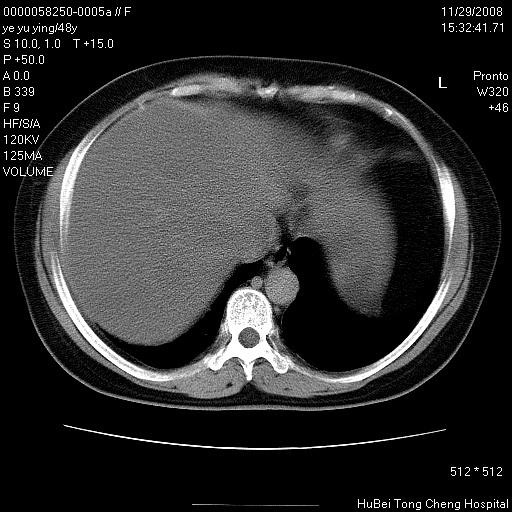

以下是引用zsl6918在2008-11-29 21:47:00的发言:[br]恶性肿瘤病史,转移瘤首先考虑。脂肪肝,胆囊结石。

以下是引用huenhao在2008-11-29 22:11:00的发言:[br]脂肪肝,胆囊结石。左肺病灶建议定期复查。

以下是引用liuyue在2008-11-30 5:44:00的发言:[br]1.左肺病变,首先考虑感染性病变,转移待排;建议治疗后复查。[br]2.肝脏密度普遍减低,考虑与化疗有关。[br]3.胆囊结石.